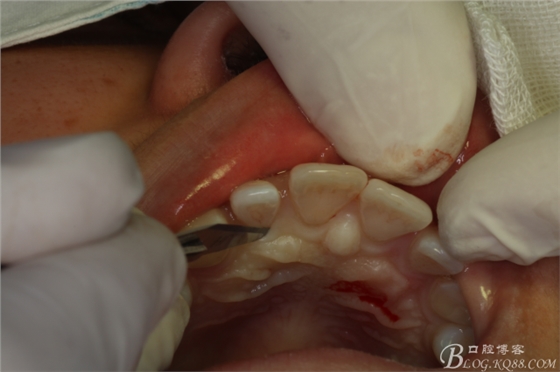

圖5.唇、腭側(cè)局部無(wú)痛浸潤(rùn)麻醉